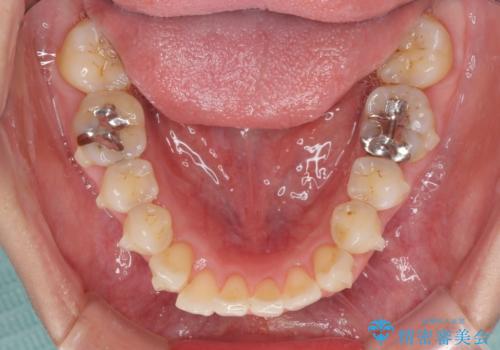

- 前歯のデコボコを気にして来院された患者様です。

上下前歯の先端同士が接触する切端咬合であったため、上顎は歯列を拡大し、下顎はIPR(歯と歯の間を削る)により叢生を解消しながら歯列を小さくすることとしました。

矯正装置にはインビザラインを用いることとしました。

治療途中に前歯に歯髄充血を思わせる痛みが認められたため、無理のない歯の移動と頻繁な経過観察を行いました。

切端咬合はスムーズに解消され、前歯の負担を軽減させることができました。